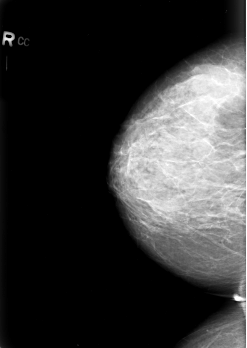

B_3029_1.LEFT_CC

LEFT_CC LINES 5608 PIXELS_PER_LINE 4080 BITS_PER_PIXEL 12 RESOLUTION 50 OVERLAY

RIGHT_CC LINES 5568 PIXELS_PER_LINE 3944 BITS_PER_PIXEL 12 RESOLUTION 50 NON_OVERLAY